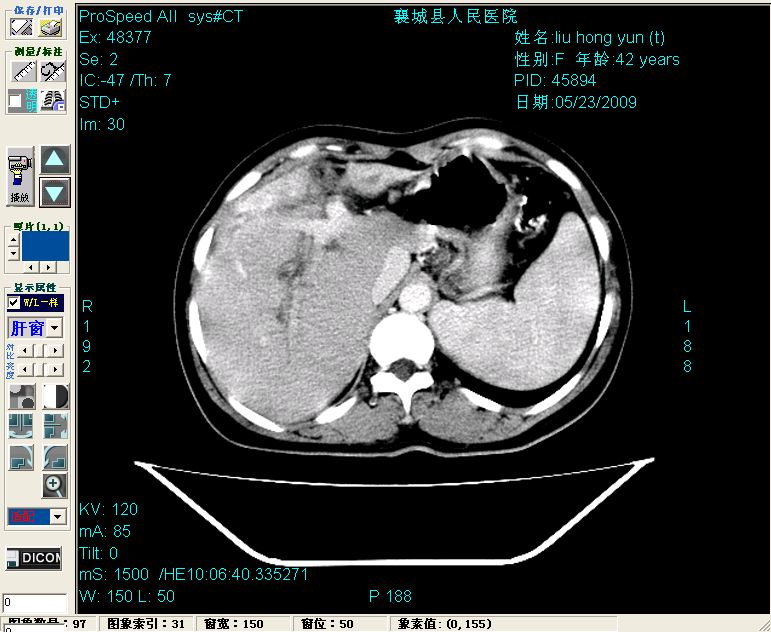

平扫:

平扫左肝外叶体积显著减小,左肝外叶见多房囊性低密度区,左肝实质及右肝前叶浅表实质呈低密度改变,左肝及右肝前叶胆管扩张,脾大

2左肝及右肝前叶表现考虑胆囊摘除术后所致的肝动门脉瘘形成,慢性纤维组织炎性增生.不完全除外左肝胆管细胞癌